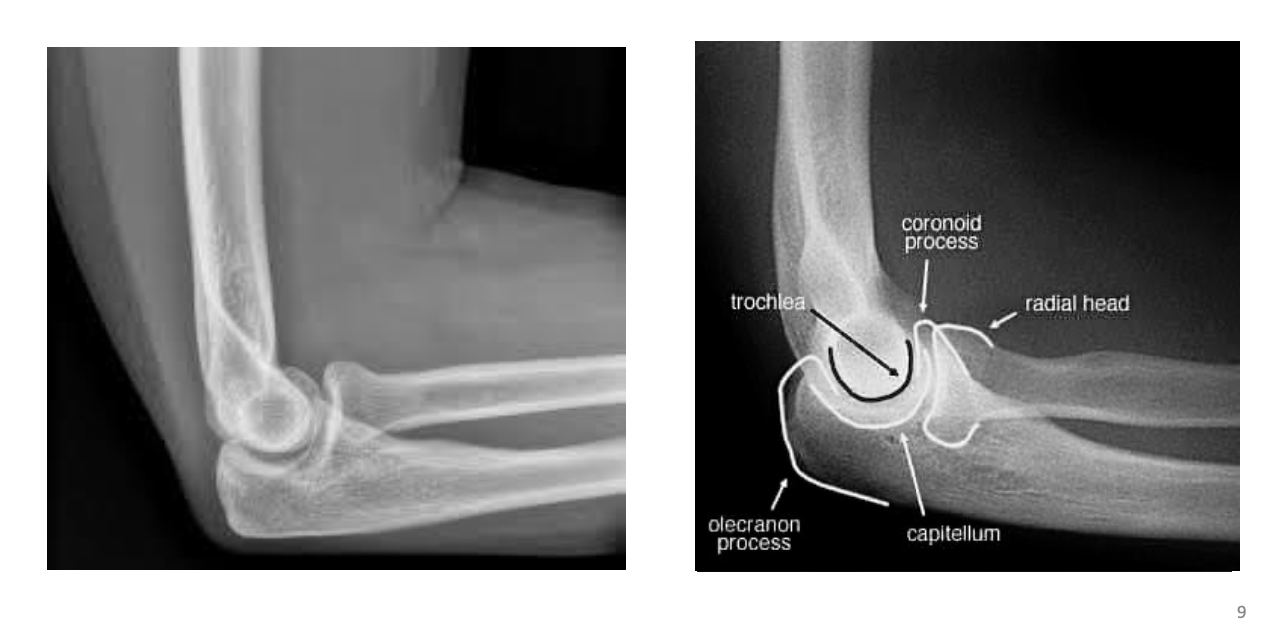

Identify the structures ? view?

AP

Elbow Joint

Elbow Joint, Lateral View